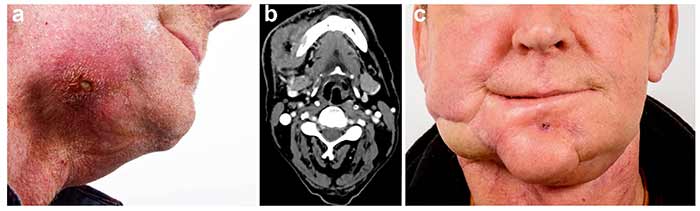

بزرگترین بازسازی فک در سال ۲۰۲۵، روی بیماری ۴۲ ساله با تومور آملوبلاستوما انجام شد. دکتر عبدلیزاده، با تیمی ۲۰ نفره، ۱۶ ساعت جراحی کرد تا فک پایین را با گرافت استخوانی از لگن و پروتزهای زیستسازگار جایگزین کند. نوآوری کلیدی، استفاده از هیدروژلهای حاوی سلولهای بنیادی برای بازسازی عروق بود، که خونرسانی را ۶۰ درصد بهبود بخشید.

این عمل، که ۷۰ درصد ساختار صورت را درگیر کرد، بیمار را از ناتوانی کامل به زندگی مستقل رساند.